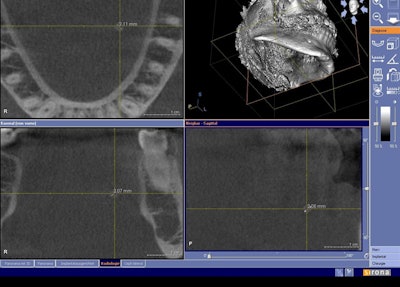

![]() Cone-beam CT dataset showing a 2-mm salivary calculus in the left submandibular gland area in the axial (upper left), coronal (lower left), and sagittal (lower right) view. Clinical and conventional 2D diagnosis failed here due to the small size of the calculus. |